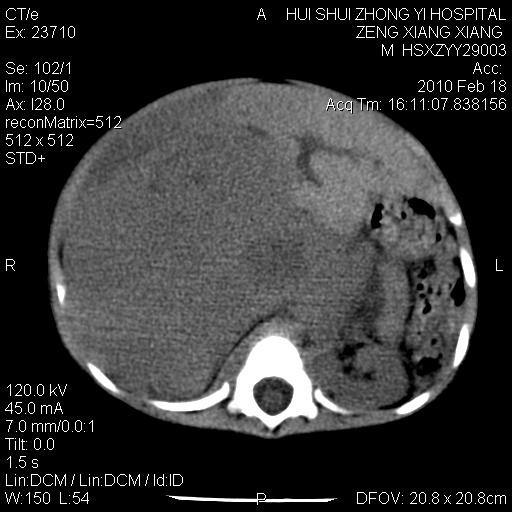

标题: PED3106:男,2岁,腹胀1月。 [打印本页]

标题: PED3106:男,2岁,腹胀1月。

定位腹膜后,肾上腺来源;

定性:恶性神经源性,肾上腺神经节母细胞瘤可能性大。

鉴别:肝母、肾母、肝脏中胚层错构瘤。

依据:年龄、有钙化,肾脏及肝脏受压移位。

肝母细胞瘤可能性大,右肾形态大体可见,不支持肾母细胞瘤,右肾移位不明显,肾上腺神经母细胞瘤可能性不大。